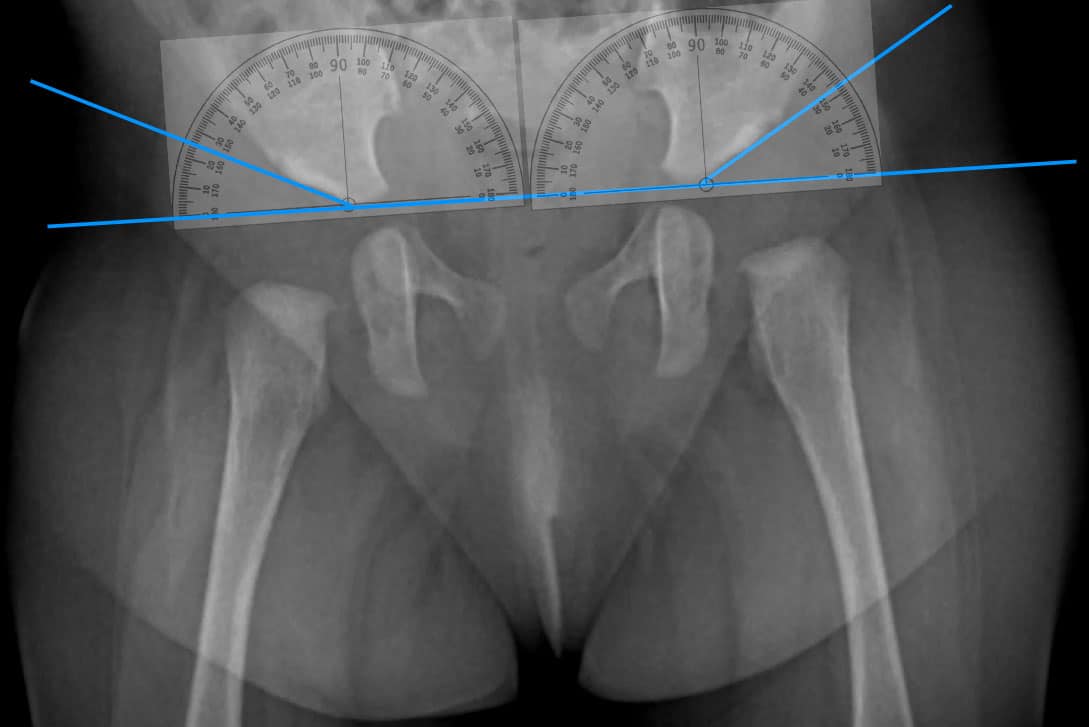

Рентген ТБС: Нормальные показатели

Раздел: Необычные решения